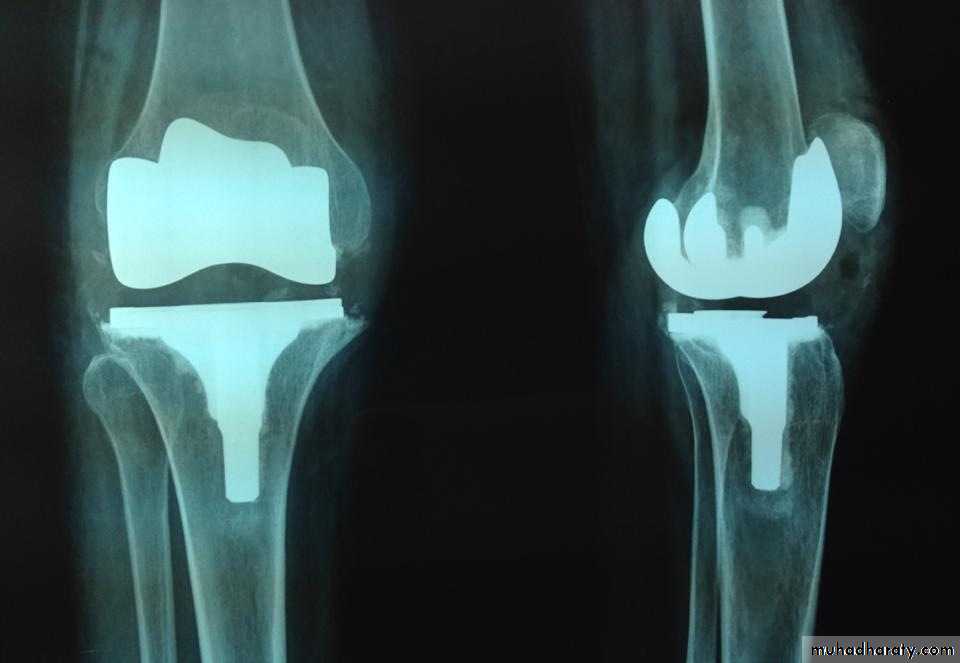

3-Replacement arthroplasty is indicated in older

patients with progressive joint destruction. This isusually a ‘resurfacing’ procedure, with a metalfemoral condylar component and a metal-backed polyethylene table on the tibial side.